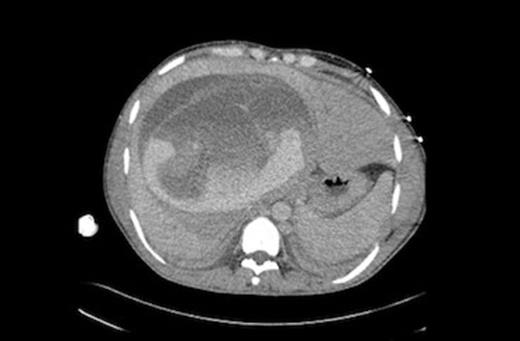

On admission he was tachycardic and had increasingly severe abdominal pain. His haemoglobin (Hb) decreased from 15 to 10.7g/dl. A CT scan revealed a large mass in the right lobe of the liver with associated haemorrhage. Urgent transfer to our Liver intensive care unit (LITU) was arranged with packed cells, fresh frozen plasma (FFP) and platelets all being transfused. He was noted to be erythematous and was suspected to have had a drug or transfusion reaction and thus received chlorphenamine.

Repeat CT scan and angiography (Figures 1&2) revealed a 17cm mass occupying the right lobe of the liver with evidence of intrahepatic arterial and portal venous contrast extravasation. There was disruption of the normal right portal venous anatomy with the left portal vein being visible but displaced. Two arterial bleeding points were embolized. The underlying nature of the mass was unknown.

CT scan showing a large liver mass with associated haemorrhage. Detached laminated membrane is visualised.